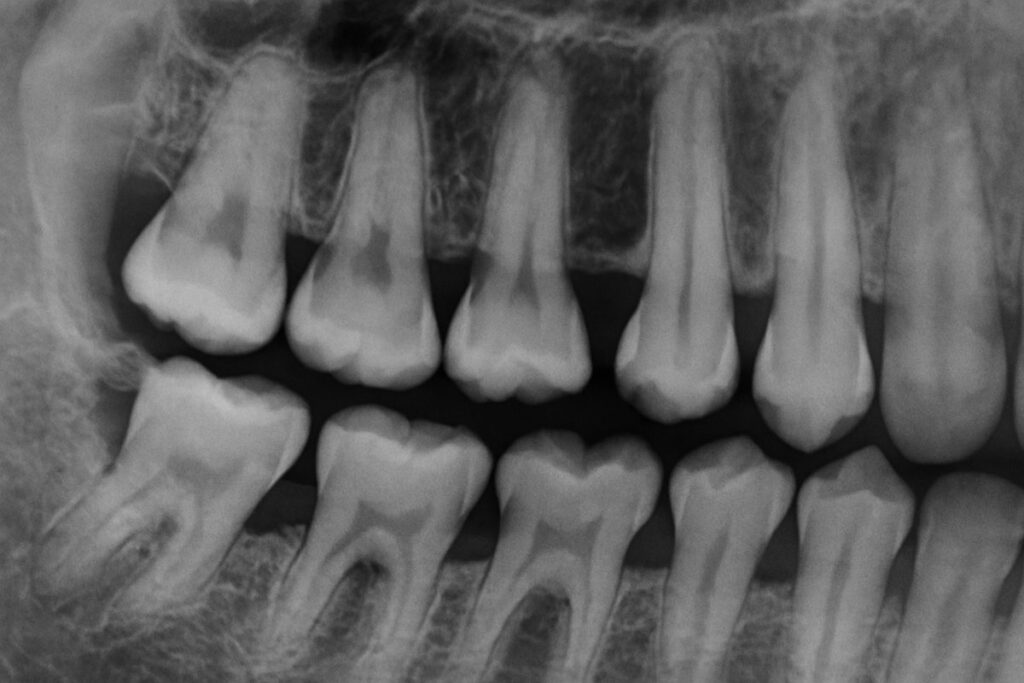

An x-ray of a jaw bone with visible bone loss around the teeth. No text on image.

What Causes Bone Loss In Your Mouth? Gum Disease, Explained.

What Causes Bone Loss In Your Mouth? Gum Disease, Explained. Intro — define and preview Bone loss in the jaw weakens the support for your...